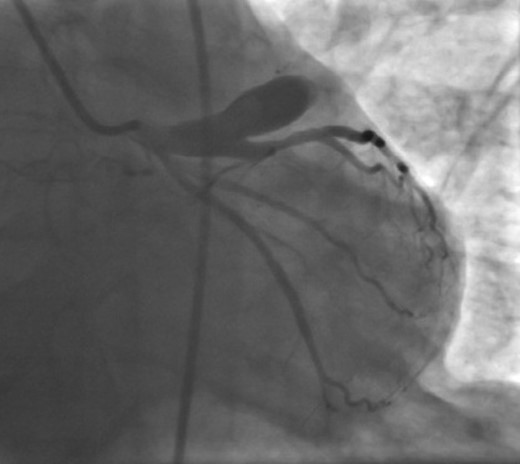

Coronary angiography was performed next day. It revealed a large (1.5 cm × 3 cm) aneurysm in the proximal part of left anterior descending coronary artery (LAD) with significant stenosis at its mid part (Fig. 2). The patient underwent successful resection of the giant aneurysm by coronary artery bypass surgery, using left internal mammary artery to bypass LAD. The patient had a usual course of hospitalization and discharged without any complications. At 6 months of follow-up, he has been asymptomatic.

Coronary angiography showing giant coronary aneurysm originating from the proximal part of left anterior descending coronary artery.